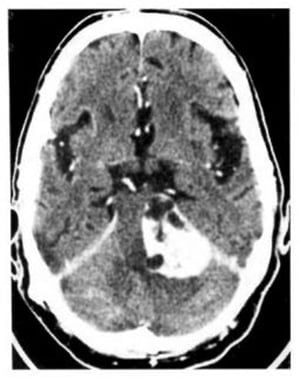

Hình 1.70. U bao Schwann thần kinh thính giác nằm ở góc cầu tiểu não trái và bắt mạnh chất cản quang.